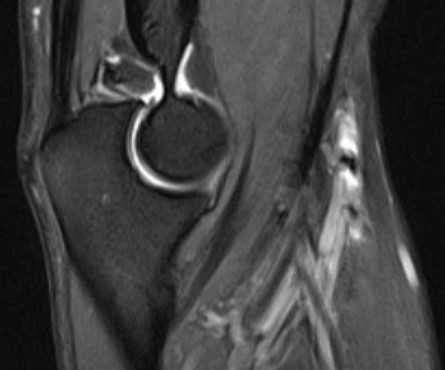

МРТ локтевого сустава в сагиттальной плоскости. Отмечается повышенное скопление свободной синовиальной жидкости в полости локтевого сустава. Синовиальная оболочка умеренно гипертрофирована.